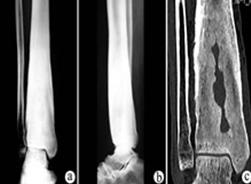

专家表示,硬化性骨髓炎又名Garre's病,特发性骨皮质硬化和干性骨髓炎,此病较少见。病因不明,不易找到致病菌。有时可能与损伤有关。损伤产生骨膜下血肿,形成钙化,本病多发生在青壮年,男多于女,体质多健壮,如运动员。长管骨均多发病,但下肢以胫骨最为多见。